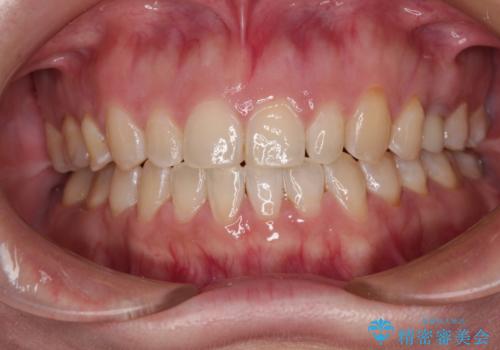

目立つ金属をすべてセラミックに 全顎的メタルフリー治療